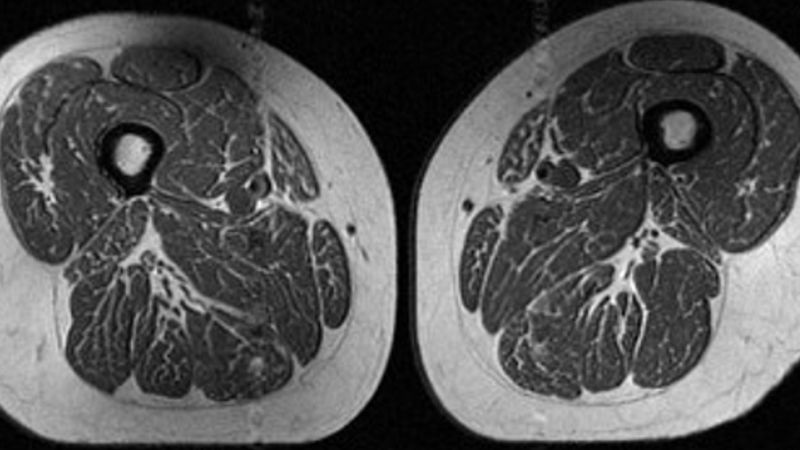

The recent findings from a study reveal striking images of fat accumulation within the thigh muscle of a 62-year-old woman, consuming 87% of her annual calories from ultraprocessed food, highlighting a concerning trend in dietary habits, reports BritPanorama.

A 61-year-old woman in the study exhibited similar, albeit less intense, fat marbling in her thigh muscles, with 29.5% of her diet comprising ultraprocessed items. This indicates that even lower levels of such dietary intake can manifest in detrimental health consequences.

The study published in the journal *Radiology* analyzed MRI scans from 615 participants in the Osteoarthritis Initiative. Notably, none exhibited signs of knee osteoarthritis but did show significant levels of intramuscular fat. With an average age of 60, participants had a BMI averaging 27, categorizing them largely as overweight.